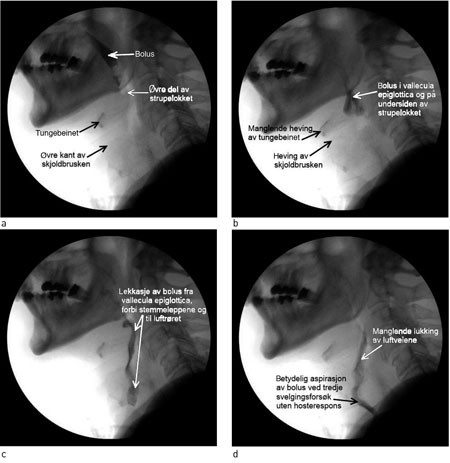

Skade av spyttkjertler (glandula parotis, submandibularis, sublingualis) gir endring i mengde og sammensetning av produsert spytt. Reduksjon av mengden av enzymer kan indirekte gi redusert tyggeevne og svelgefunksjon, og gi munntørrhet som medfører økt risiko for karies. Osteoradionekrose kan også oppstå og øke pasientens plager i form av henfall av beinsubstans, tannløsning og sår i slimhinner over kjevebeinet som ikke vil gro. Stråleterapi gir fibrose og arrdanning. Dette leder til økt rigiditet i vevet og fører til nedsatt evne til å gape. Ved uttalt fibrose kan det oppstå strikturer i svelg og spiserør. I tillegg kan dette føre til redusert styrke i tungemuskulatur og nedsatt koordinasjon av tungebevegelser, redusert evne til å presse tungeroten mot bakre svelgvegg og nedsatt heving av strupehodet i forbindelse med svelging. Konstriktormuskulaturen i pharynx kan påvirkes, med redusert evne til videretransport av bolus som følge. Strupelokkets bevegelighet svekkes. Det medfører redusert evne til å stenge for luftveiene under svelgeprosessen. Tilstanden ledsages også ofte av nedsatt sensibilitet. Dette kan vanskeliggjøre utløsing av svelgerefleks og evne til rensing av pharynx. Pasientene kan derved aspirere uten at de merker det (fig 1, video). Strålebehandling kan gi lymfødem som skyldes opphoping av lymfe interstitielt som følge av destruksjon av lymfekar. Mukositt, inflammasjon i de mukøse membranene, oppstår oftest i den første fasen etter stråleterapi. Tilstanden kan være svært smertefull, og reduserer pasientens mulighet til å innta fast næring og væske (4, 5).

Figur 1  Bilder fra videofluoroskopiopptak av kreftpasient etter strålebehandling. Bildene (a – d) viser orofaryngeale…

Figur 1 Bilder fra videofluoroskopiopptak av kreftpasient etter strålebehandling. Bildene (a – d) viser orofaryngeale svelgevansker som fører til aspirasjon